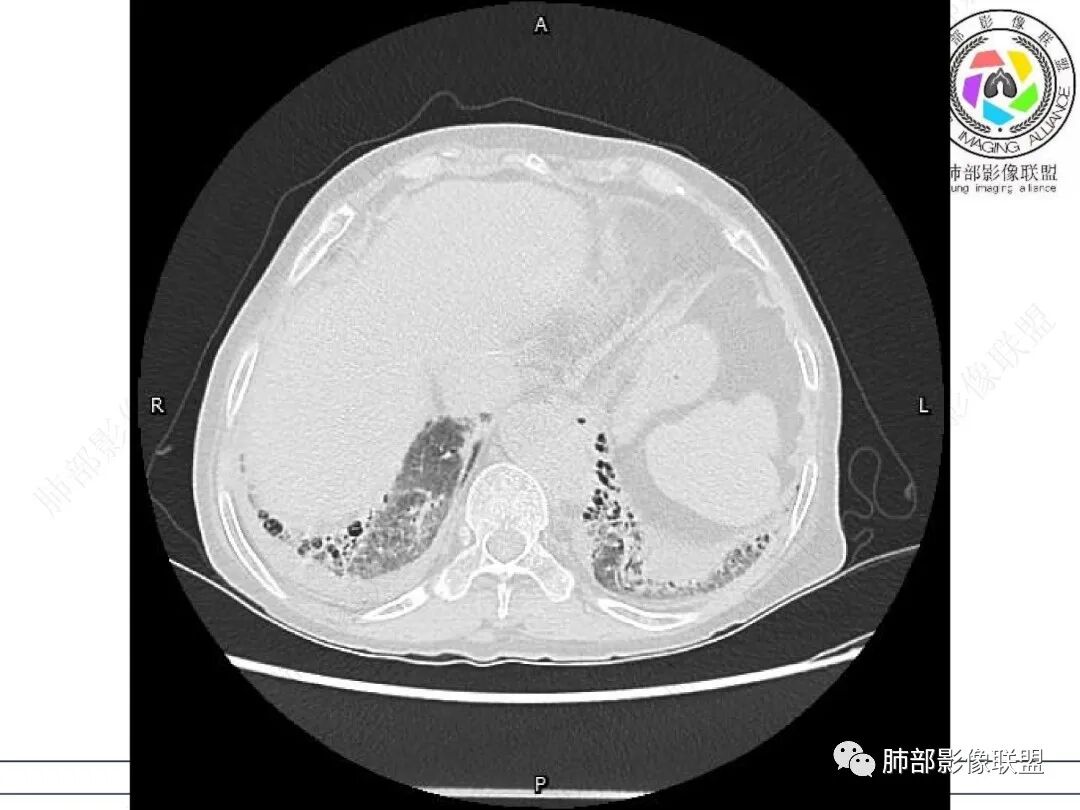

①影像表现复杂:较弥漫间质性改变,对称磨玻璃密度为主,小叶间隔增厚,有一定重力分布趋势,未见明显纤维化,气囊及蜂窝位于肺边缘,未见典型“月弓征”。心脏影增大,双侧胸腔积液。

患者存在肺水肿应当是合理的解释。其他旁证还有,心脏影增大,肾小球滤过率降低,双侧胸腔积液等等……

实验室白细胞不高,C反应蛋白、PCT增高,淋巴细胞显著低(CD4项阙如),G试验值相当高。肾小球滤过率降低,呼衰等等。